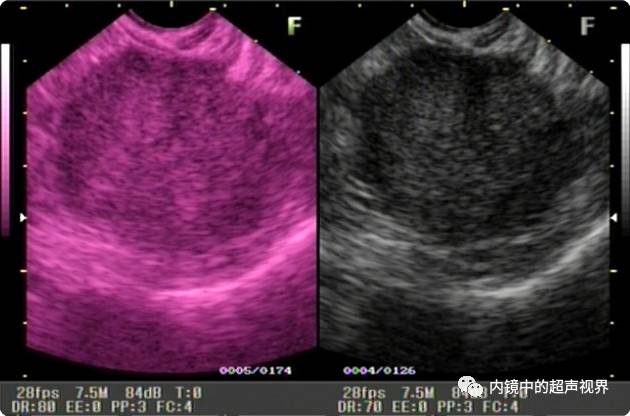

再来一张间质瘤的图片,也是DR30和80的对比。

有没人觉得,这个间质瘤的图片跟前面两个病灶不太一样,似乎感觉高DR模式看起来更舒服,那是因为,间质瘤为低回声,它周围的软组织为高回声,本身就能形成良好的对比,无需降低DR,而高DR模式更显细腻。

间质瘤